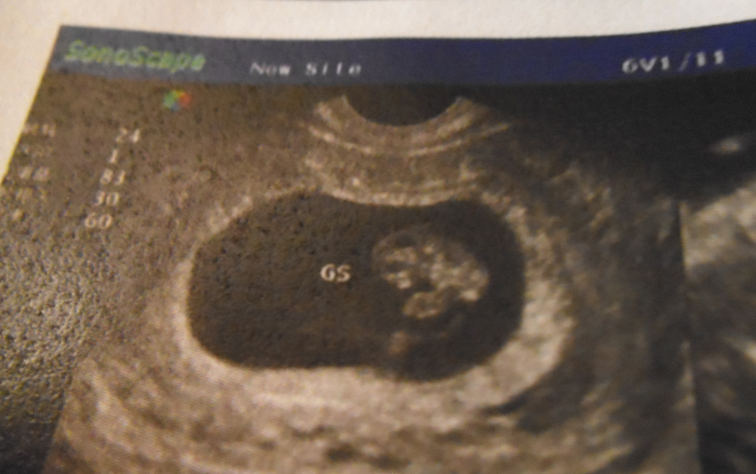

你好,我的超声检查报告单上显示的是宫内早孕,约8W+,妊娠囊53×30mm,囊内见卵黄囊及胎芽,头

臀径约19mm,胎心管搏动可见,以上这些是属于正常的吗?另外还有,根据报告单上提供的图像来看,胎儿已经成形了!这也属于正常的吗?

病情分析: 根据您的检查看胎儿和停经月份是相符合的,建议您及时观察对症治疗 指导意见: 必要的情况下需要及时化验血尿常规肝功能等等产前检查,及时注意避免生冷辛辣油腻的食物就可以了